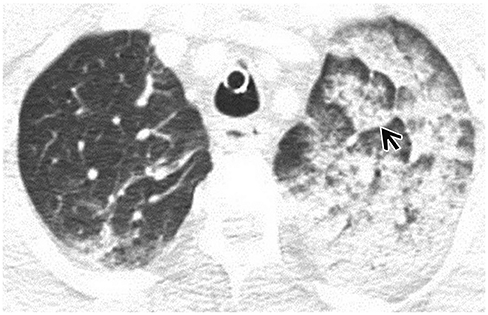

Computed Tomographic Features of Lung Parenchyma Over Time after Cardiopulmonary Resuscitation

To identify the key CT features of lung parenchyma over time after cardiopulmonary resuscitation (CPR).

In total, 72 patients underwent CT after CPR. Because the median time from return of spontaneous circulation (ROSC) to CT was 1 h 3 min, we divided patients into two groups: ≤ 1 h (group 1) and > 1 h (group 2), based on the ROSC to CT time. We analyzed and compared various lung parenchymal CT findings between groups.

Each group included 36 patients. Using statistical analysis, we identified seven statistically significant imaging features. Gradient (p = 0.010), lobular gradient (p = 0.017), diffuse pattern (p = 0.000), upper distribution (p = 0.032), and peripheral portion sparing (p = 0.000) were more common in group 1 than in group 2. Dependent density (p = 0.010) and lobular consolidation (p = 0.010) were more common in group 2 than in group 1.

The gradient and lobular gradient tended to disappear over time after ROSC. In terms of distribution, a diffuse pattern with upper predominance and peripheral portion sparing tended to disappear over time. However, the dependent density and lobular consolidation tended to increase over time in the lung parenchyma after CPR.